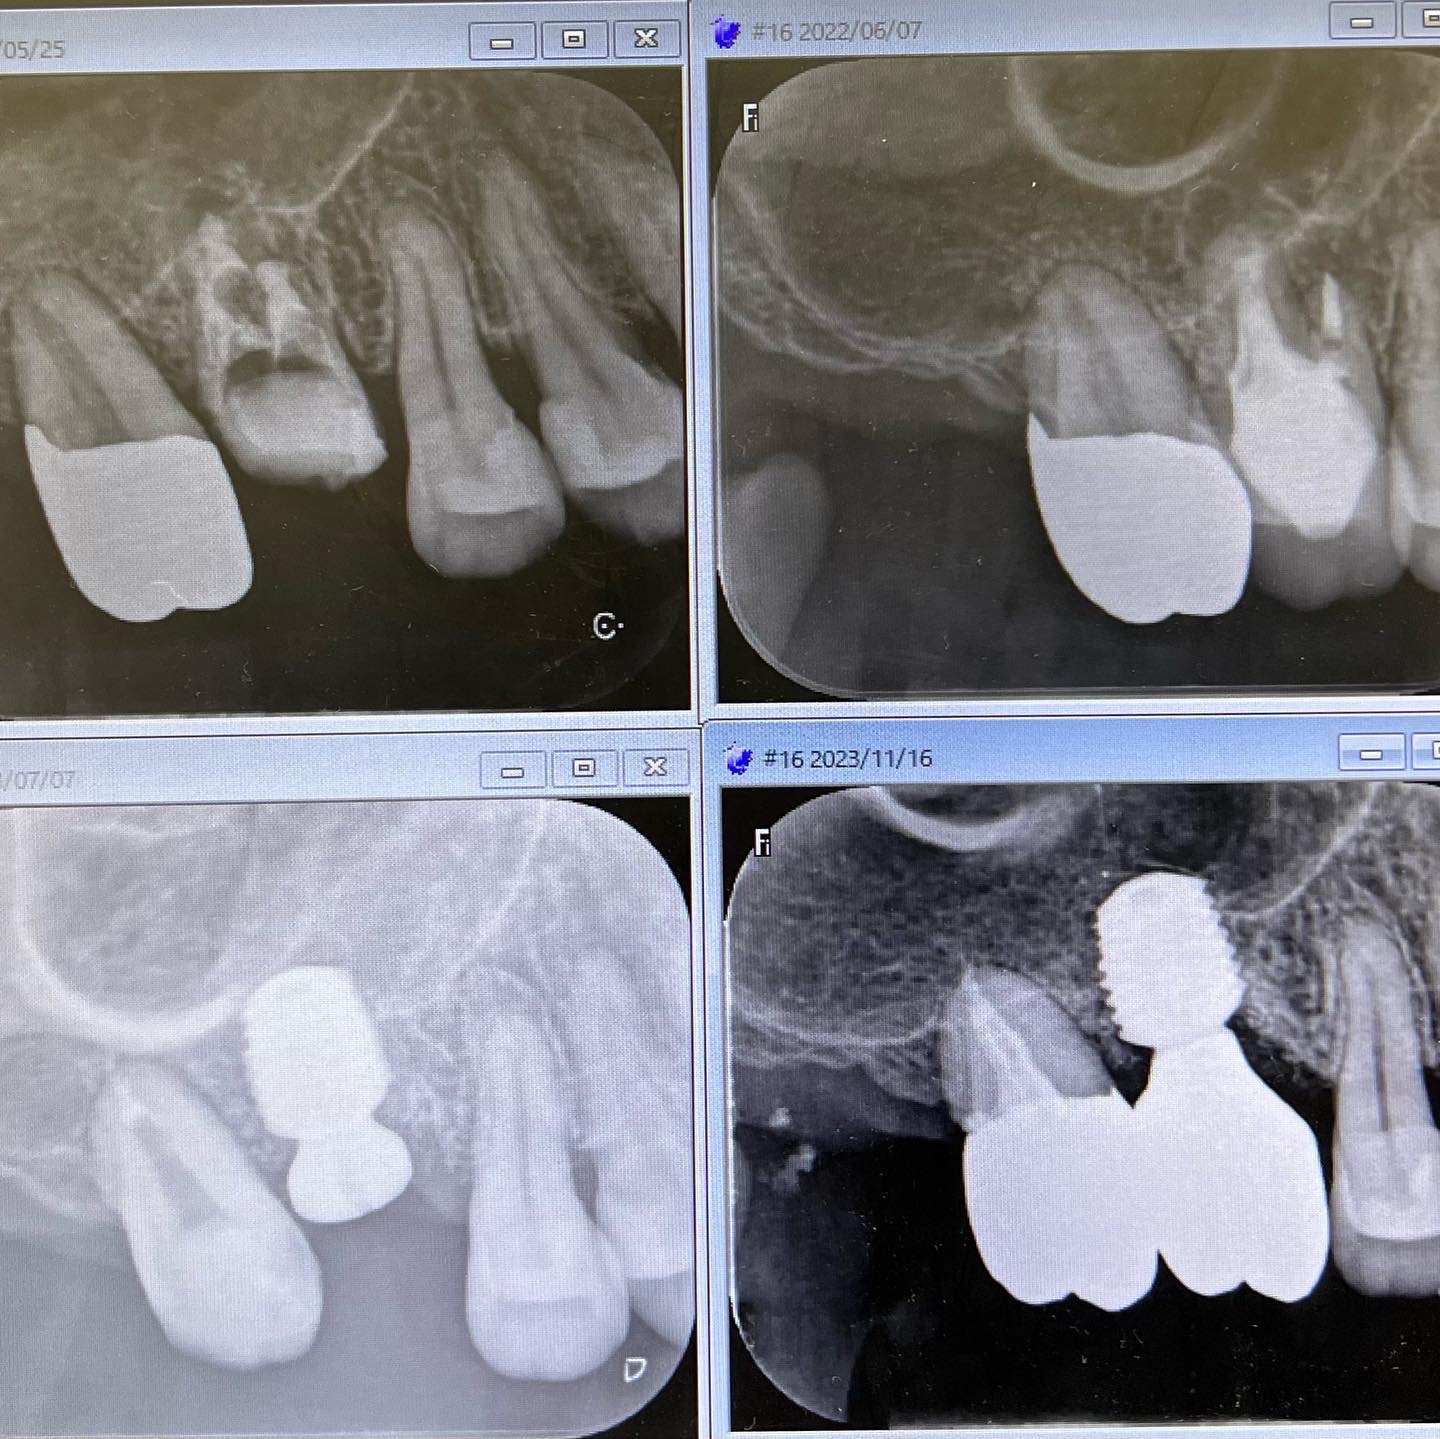

インプラント上部構造やり直し

2024/04/28症例